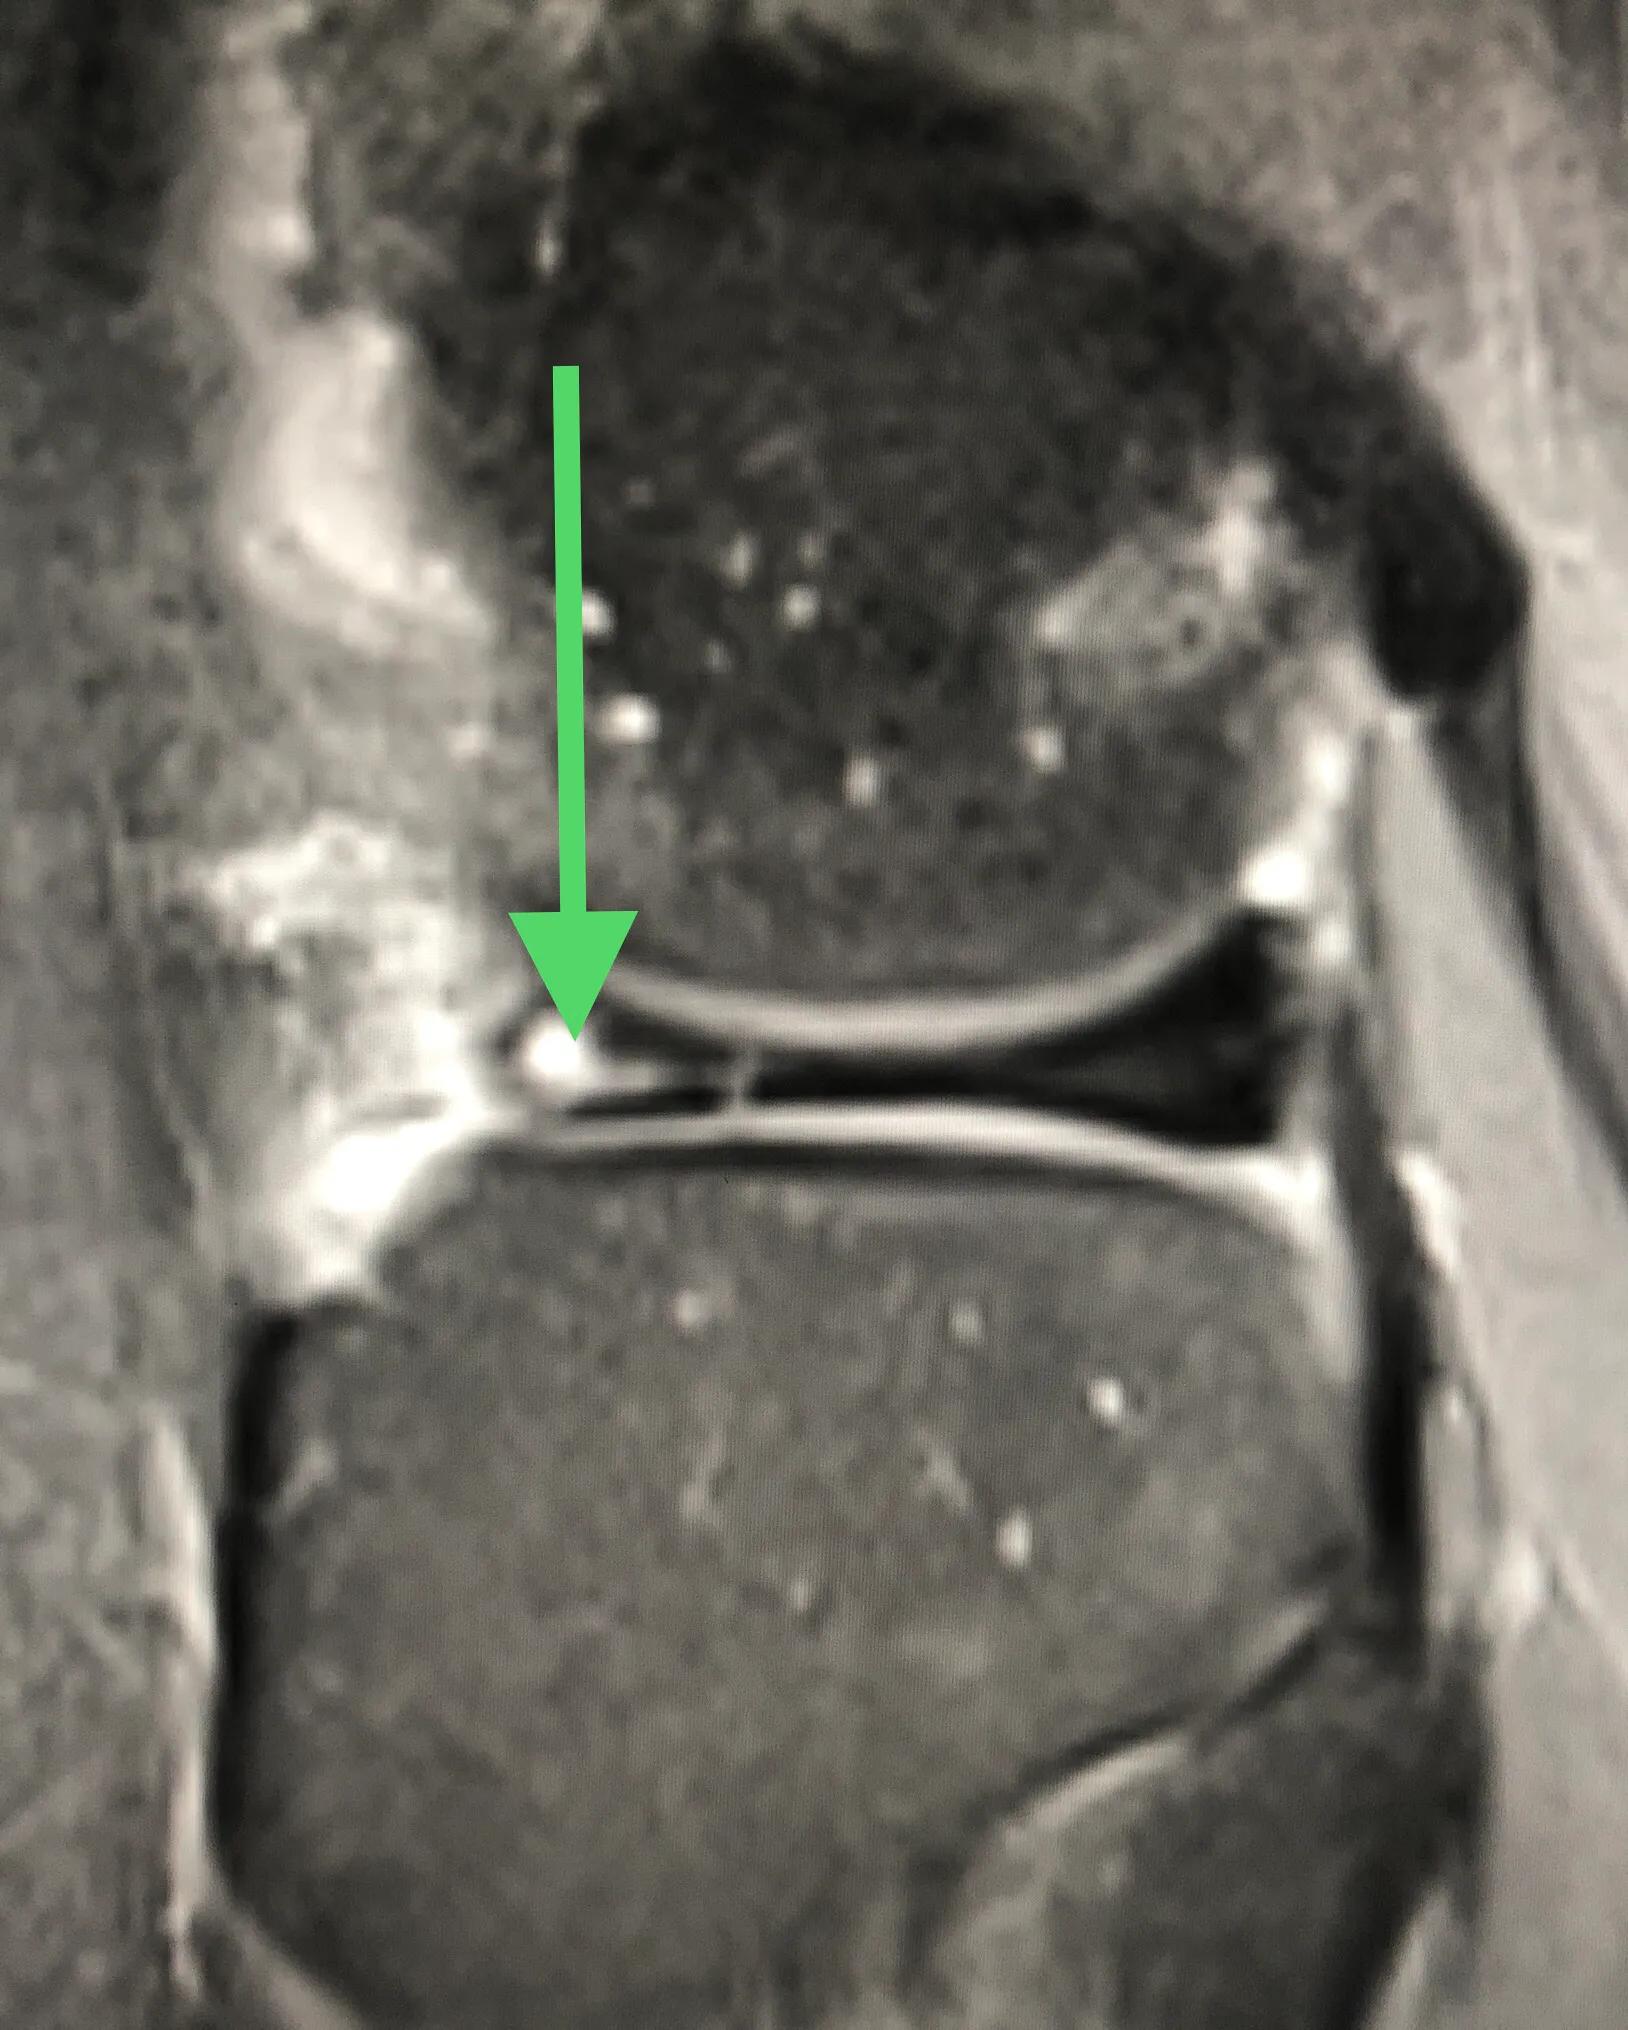

换个方向看肥厚的盘状半月板,绿箭头之间的那块便是,已经撕裂,需要手术。

这个也是撕裂的半月板。